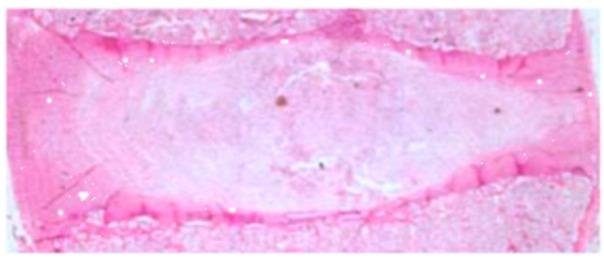

Intervertebral disc degeneration (IVDD) is a complex and progressive process of disc aging. One of the most important causes of changes in the internal environment, leading to IVDD, can be changes in the concentration of individual metal elements. This study aimed to analyze the concentrations of copper, iron, manganese, lead, zinc, sodium, potassium, phosphorus, and calcium in the degenerated intervertebral discs of the lumbosacral spine, compared to healthy intervertebral discs. The study group (S) consisted of 113 Caucasian patients, qualified by a specialist surgeon for IVDD of the lumbosacral spine. The control group (C) consisted of 81 individuals. The biological material was obtained from Caucasian human cadavers during post-mortem examination. The concentrations of individual elements were assessed using inductively coupled plasma−optical emission spectroscopy (ICP-OES). Statistically significant differences in the concentrations of microelements, depending on the degree of pain intensity, were noted for only potassium (p < 0.05). Statistically significant differences in the concentrations of the assessed microelements, depending on the degree of radiological advancement of the lesions, were noted for copper and iron (p < 0.05). In the degenerated intervertebral discs, the strongest relationships were noted between the concentrations of zinc and lead (r = 0.67; p < 0.05), zinc and phosphorus (r = 0.74; p < 0.05), and zinc and calcium (r = 0.77; p < 0.05). It has been indicated that, above all, the concentrations of copper and iron depend on the advancement of radiological changes, according to the Pfirrmann scale; however, no influence on the pain intensity, depending on the concentration of the assessed elements, was found.

椎间盘退行性变(IVDD)是椎间盘老化的复杂进行性过程。导致 IVDD 的内部环境变化的最重要原因之一是个别金属元素浓度的变化。本研究旨在分析腰椎间盘退行性变患者的椎间盘与健康椎间盘相比,铜、铁、锰、铅、锌、钠、钾、磷和钙的浓度。研究组(S)由 113 名白人患者组成,这些患者均由骨科专家确诊为腰椎间盘退行性变。对照组(C)由 81 名个体组成。生物材料是在死后检查过程中从白人尸体中获得的。使用电感耦合等离子体-发射光谱法(ICP-OES)评估个别元素的浓度。仅在钾(p<0.05)方面,根据疼痛强度程度,注意到了微量元素浓度的统计学显著差异。根据病变放射学进展程度,注意到了铜和铁(p<0.05)的评估微量元素浓度的统计学显著差异。在退行性椎间盘,锌和铅之间(r=0.67;p<0.05)、锌和磷之间(r=0.74;p<0.05)以及锌和钙之间(r=0.77;p<0.05)观察到最强的相关性。研究表明,根据 Pfirrmann 分级,尤其是铜和铁的浓度取决于放射学变化的进展;然而,根据所评估元素的浓度,未发现对疼痛强度的影响。